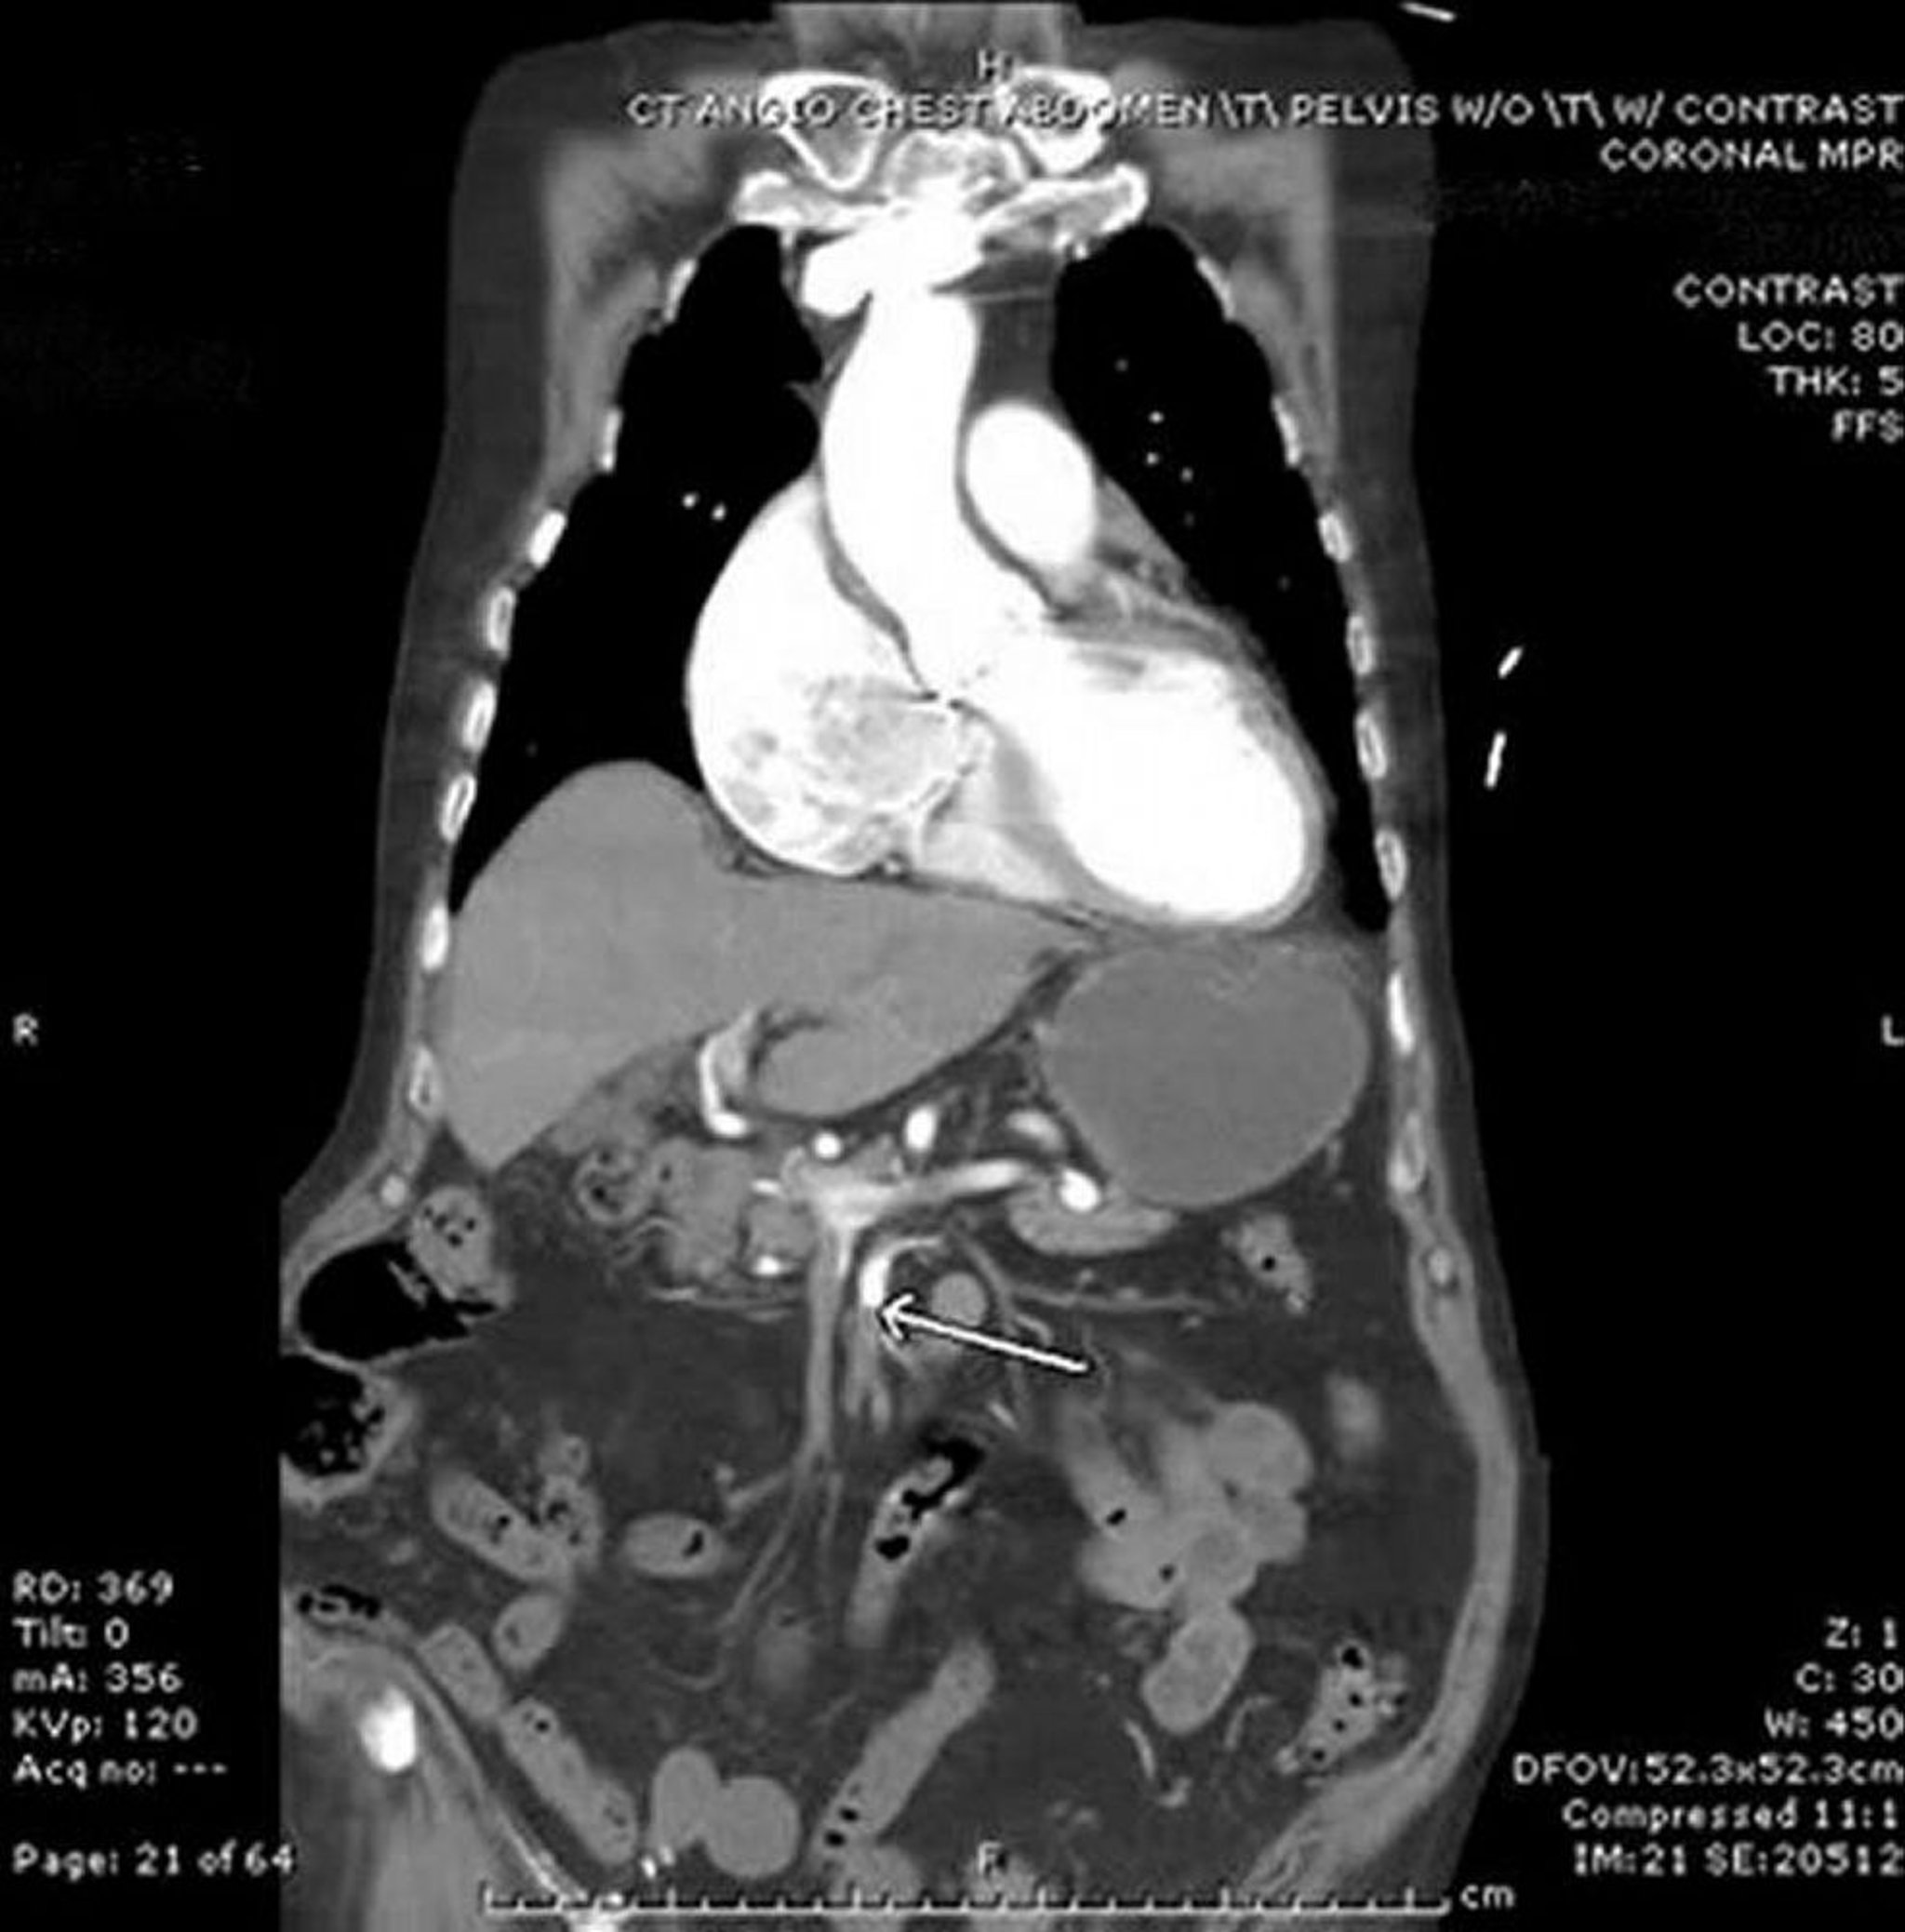

Ischémie mésentérique (Angio-TDM)

Dans cette image, la flèche pointe vers l'artère mésentérique supérieure, qui présente une interruption brusque du contraste IV. On observe un épaississement de l'intestin grêle dans l'abdomen gauche. Ce cas d'embolie est d'origine cardiaque chez un patient qui a une fibrillation auriculaire.

Image provided by Parswa Ansari, MD.